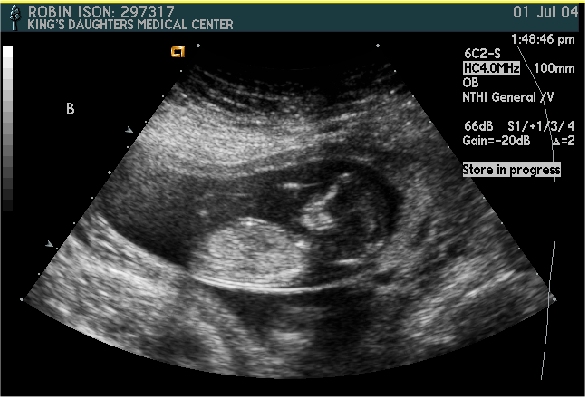

Baby A or B - I am not sure.

Pictures from Ultrasound at 13 1/2 weeks.